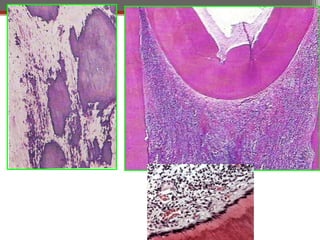

Periapical inflammation

Periapical

Granuloma

abscess

Chronic abscess or

osteomyelitis

Cellulitis

Skin or mucosal sinus

Bacteremia

Cyst

Periapical inflammation Periapical Granuloma Periapical abscess Chronic abscessor osteomyelitis Cellulitis Skin or mucosal sinus Bacteremia Periapical Cyst